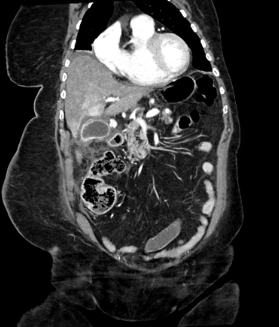

• Phình động mạch tạng (Visceral Artery Aneurysms - VAA)

• Phình động mạch thân tạng (Celiac Artery Aneurysm - CAA)

• Phình động mạch mạc treo tràng dưới (Inferior Mesenteric Artery - IMA Aneurysm)

• Phình động mạch lách (Splenic Artery Aneurysm - SAA)

• Phình động mạch gan (Hepatic Artery Aneurysm - HAA)

• Phình động mạch thận (Renal Artery Aneurysm - RAA)